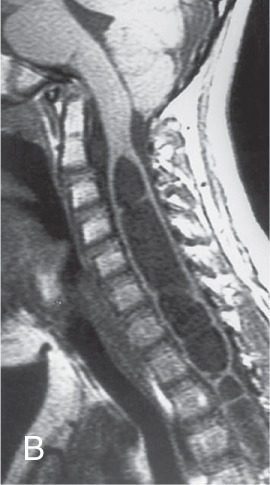

Dị tật Arnold-Chiari II (A-C II) (Hình 48.7)

Rỗng tủy (Hydromyelia) (Hình 48.7)

Hình 48.7 MRI Dị tật Arnold-Chiari II (A-C II)

(Hình ảnh MRI (A) cho thấy dị tật Chiari II và (B) cho thấy rỗng tủy)

- Dị tật Chiari II có triệu chứng vẫn là nguyên nhân gây tử vong hàng đầu cho trẻ sơ sinh bị MMC.

- Rỗng tủy (Hydromyelia): Sự giãn nở của ống trung tâm tủy sống. Khi có triệu chứng, nó thường biểu hiện bằng vẹo cột sống tiến triển nhanh, thay đổi sức mạnh hoặc phối hợp của chi trên hoặc chi dưới, và co cứng. MRI là xét nghiệm tốt nhất để chứng minh bất thường tủy sống này.